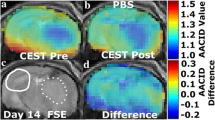

AACID CEST maps were acquired in all animals 11 ± 1 days after U87MG cancer cell implantation. Anatomical FSE MR images were successfully used to identify regions of interest in the tumor and on the contralateral side (Figs. 1c and 2c). AACID CEST maps showed the expected lower AACID value in the tumor region compared to the surrounding brain tissue (Figs. 1a and 2a) indicating a relatively basic intracellular tumor pH. Also, as expected, a large increase in tumor AACID value was observed within the tumor following the injection of the drug combination (Fig. 1b) indicating rapid intracellular acidification within 2 h of injection. As expected, the difference between the post and pre images in a single animal showed a greater effect in the tumor ROI compared to the contralateral ROI (Fig. 1d). Specifically, two hours after injection of the drug combination, there was an average increase in the AACID value of 0.10 ± 0.03 (N = 6, p < 0.05) in the tumor region (Fig. 3a), but no change in AACID value within the contralateral tissue (Fig. 3a). When providing glucose prior to the combined drug injection an even larger increase in AACID value was visible (Fig. 2b) suggesting even greater acidification was achieved. When pre-treating with glucose, there was a significant increase in the AACID value of 0.18 ± 0.03 (N = 6, p < 0.0001) two hours after the combination drug injection in the tumor region (Fig. 3b). However, there was also a small change in the AACID value within the contralateral tissue (Fig. 3b). The difference between the post and pre images in a single animal (Fig. 2d) showed a greater effect in the tumor ROI compared to the contralateral ROI as expected. The measured changes in the average AACID value within the tumor after the combination drug treatment corresponded to a 0.4 pH drop, while pretreatment with glucose produced a 0.72 pH drop, estimated using Eq. 2.

Mouse brain with GBM tumor 11 ± 1 days after implantation: a baseline AACID map prior to drug injection, b the AACID map two hours post drug injection, c coronal fast spin-echo anatomical image showing the ROIs in the tumor (dashed white line) and on the contralateral side (solid white line), and d AACID difference maps for the same brain post–pre drug injection

Mouse brain with GBM tumor 11 ± 1 days after implantation: a baseline AACID map prior to drug and glucose injections, b the AACID map two hours post drug and glucose injections, c coronal fast spin-echo anatomical image showing the ROIs in the tumor (dashed white line) and on the contralateral side (solid white line), and d AACID difference maps for the same brain post–pre drug and glucose injections